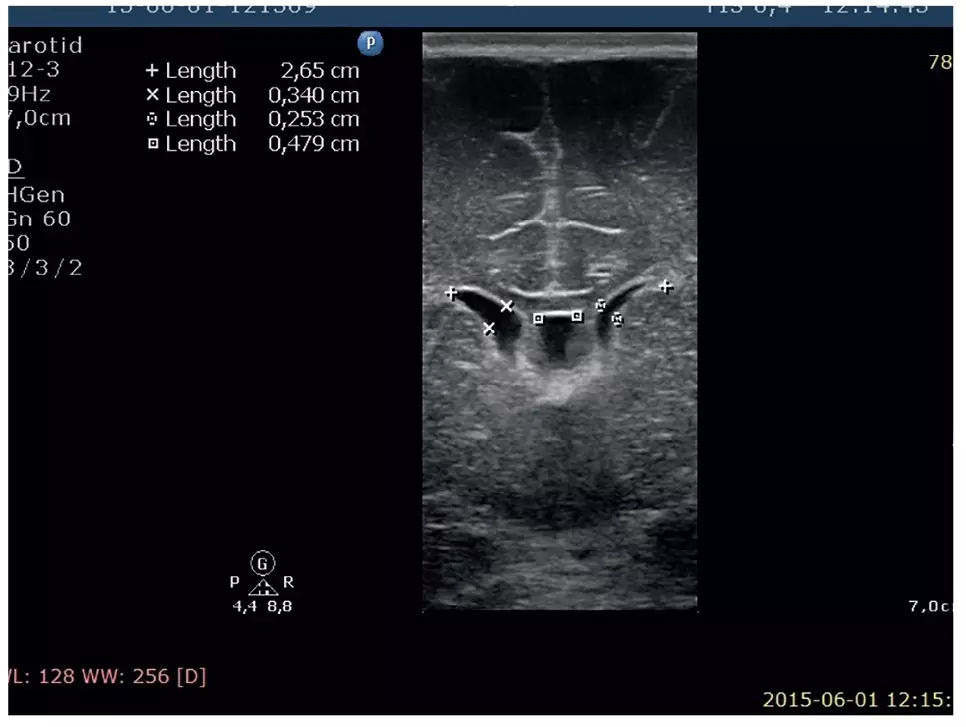

Ryc. 1. Asymetria komór bocznych bez poszerzenia L > P, jama przegrody przezroczystej

Dziecko urodzone w stanie średnim, z sinicą obwodową, obniżonym napięciem mięśniowym, z zaburzeniami oddychania. Na sali porodowej wymagał rozprężenia płuc za pomocą maski twarzowej i układu T oraz powietrza atmosferycznego; uzyskano poprawę stanu klinicznego. Z uwagi na utrzymujące się pomimo tlenoterapii zaburzenia oddychania i kwasicę oddechową (pH 7,17, pC02 71 mmHg) zastosowano nieinwazyjne wsparcie oddechowe typu nCPAP, które kontynuowano dwie doby, uzyskując szybką stabilizację stanu ogólnego. W badaniach pomocniczych – posiew krwi jałowy. Leukocytoza 26, 28, 15 tys./ul, płytki w normie, CRP nieznacznie podwyższone z szybką normalizacją (8,18 mg/l, 5,49 mg/l, 1,96 mg/l). Aktywność w surowicy LDH 648 U/l, CK 2029, w kolejnych dobach odpowiednio 1197 i 435 U/l, CK-MB 172, 74, 67 U/l. Hiperbilirubinemia od drugiej doby z maksymalnym stężeniem bilirubiny 14,5 mg%. W rtg klatki piersiowej pola płucne bez zmian ogniskowych. W wykonanym USG mózgowia: układ komorowy nadnamiotorwy asymetryczny, nieposzerzony (P < L). Sploty naczyniaste obustronnie szersze, hyperechogenne, niejednorodne, o nierównych obrysach. Istota biała okołokomorowa o zwiększonej echogeniczności. W badaniu powtórzonym w 6. d.ż. utrzymuje się niewielka asymetria układu komorowego (P < L). Mózgowie bez zmian ogniskowych. Sploty naczyniowe komór bocznych symetryczne o gładkich zarysach. W badaniu okulistycznym: OPL – drobne wybroczyny podspojówkowe, poza tym odcinek przedni w normie, soczewki przezierne.